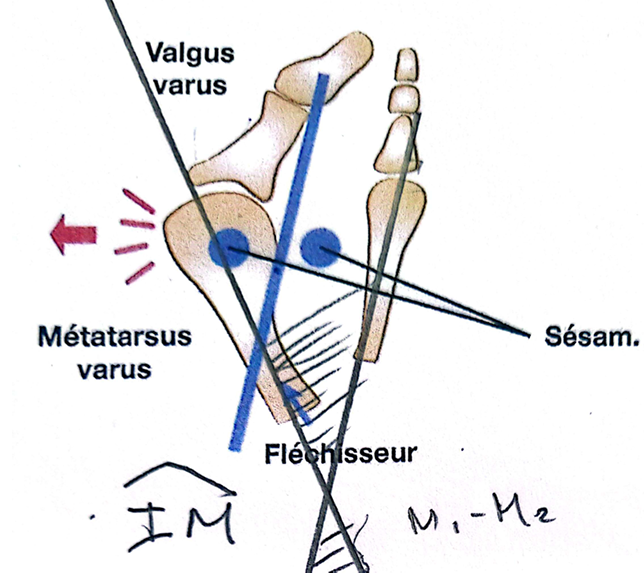

Figure 2 La déformation entraîné plusieurs anomalies

Lorsque les traitements conservateurs ne permettent plus de soulager les symptômes, une prise en charge chirurgicale peut être envisagée. Plusieurs techniques existent pour corriger l’hallux valgus. Parmi elles, l’ostéotomie bifocale percutanée représente une option intéressante dans les déformations importantes. Car cette technique corrige les 2 déformations essentielles :

a) le métatarsus varus qui se traduit par un angle M1 -M2 ou angle IM supérieur à 10° ( valeur normale < à 8°)

b) l’angle M1-P1 qui est supérieur à 20° (valeur normale de 8à 12° maximum 15°)

La première anomalie

Elle correspond à la déviation latérale du gros orteil, appelée valgus. Le gros orteil s’oriente progressivement vers les autres orteils, au niveau de l’articulation métatarso-phalangienne. Cette déviation modifie l’axe normal du premier orteil et perturbe son rôle essentiel dans la propulsion lors de la marche.

La deuxième anomalie

Elle concerne le déplacement du premier métatarsien vers l’intérieur du pied, phénomène appelé métatarsus primus varus. L’écartement progressif entre le premier et le deuxième métatarsien entraîne une perte d’alignement du premier rayon et contribue à l’aggravation de la déformation.

La troisième anomalie

Il s’agit de la «bosse» ou «l’exostose». Son siège est dorso-médial, en regard de la tête du premier métatarsien.

Elle correspond à l’hypertrophie médiale de la tête du premier métatarsien. C’est une proéminence osseuse qui est visible sur le bord interne du pied et forme ce que l’on appelle communément un « oignon ». Il ne s’agit pas d’une excroissance osseuse indépendante, mais plutôt de la conséquence de la déformation et de la saillie de la tête métatarsienne devenue plus apparente.

À ces anomalies osseuses s’ajoutent également des modifications des tissus mous autour de l’articulation. Les ligaments, la capsule articulaire et les tendons se déséquilibrent progressivement. Certains se rétractent tandis que d’autres se distendent, ce qui entretient et accentue la déviation du gros orteil.

La déformation est également favorisée par un déséquilibre des structures musculaires et tendineuses qui stabilisent l’articulation métatarso-phalangienne. Certains tendons, notamment ceux situés sur le versant latéral de l’articulation, peuvent exercer une traction qui accentue progressivement la déviation du gros orteil. Ce déséquilibre entretient et aggrave la déformation au fil du temps.

Enfin, la déformation entraîne souvent une subluxation des sésamoïdes, deux petits os situés sous la tête du premier métatarsien. Leur déplacement modifie l’équilibre de l’articulation et perturbe le fonctionnement normal du système d’appui.